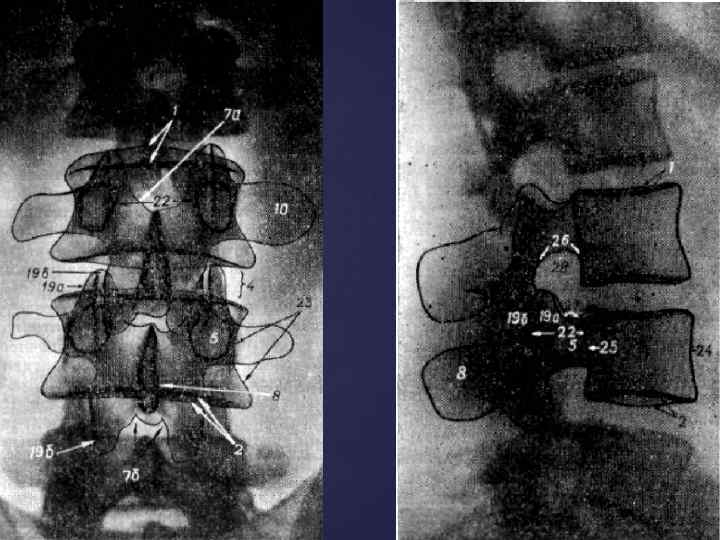

СРОКИ ОКОСТЕНЕНИЯ КОСТЕЙ ЧЕЛОВЕКА 1. ПОЗВОНОЧНИК - появление трех точек окостенения (т. о. ) (тело и две половины дуги) - внутриутробно - синостоз дуги и тела – 2 -3 года - синостоз обеих половин дуг – 1 -8 лет (в зависимости от уровня) - появление добавочных т. о. (апофизы - лимбы позвонков) – 7 -8 лет - полное слияние всех добавочных т. о. - 23 -26 лет - синостозирование крестца – 11 -12 лет

СРОКИ ОКОСТЕНЕНИЯ КОСТЕЙ ЧЕЛОВЕКА 1. ПОЗВОНОЧНИК - появление трех точек окостенения (т. о. ) (тело и две половины дуги) - внутриутробно - синостоз дуги и тела – 2 -3 года - синостоз обеих половин дуг – 1 -8 лет (в зависимости от уровня) - появление добавочных т. о. (апофизы - лимбы позвонков) – 7 -8 лет - полное слияние всех добавочных т. о. - 23 -26 лет - синостозирование крестца – 11 -12 лет